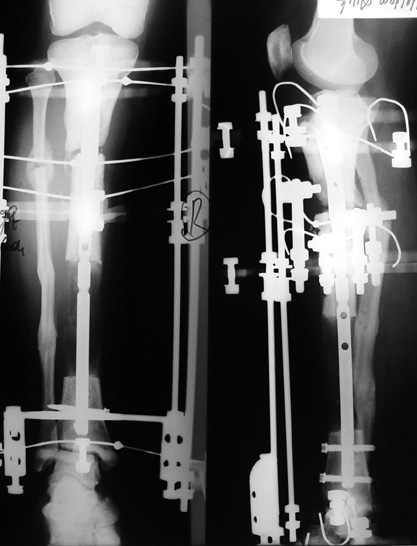

Eksternal fiksatör ile geçen süre (eksternal fiksasyon indeksi), gereken distraksiyon miktarına bağlıdır ve bu süre boyunca bazı komplikasyonlarla karşılaşılabilir. Distraksiyon dönemi sona erdikten sonra, distraksiyon süresinin iki katını aşan konsolidasyon döneminde hastalar eksternal fiksatörü zorlukla tolere edebilirler. Yeterli konsolidasyon sağlanmadan eksternal fiksatör çıkartılırsa ise kırıklar, deformite ve kısalık oluşabilir. Hastanın fiksatör ile birlikte geçirdiği sürenin azaltılması ve böylece hasta konforunun ve aktivite düzeyinin arttırılması için intramedüller çivi üzerinden uzatma yöntemi uygulanmaktadır. Bu yöntemde distraksiyon dönemi sona erdiğinde kemiğin içindeki çivi statik olarak kilitlenmekte ve eksternal fiksatör çıkartılmaktadır. Stabilizasyon intramedüller çivi tarafından sağlandıktan sonra konsolidasyon dönemi gerçekleşmektedir. Bu şekilde hem eksternal fiksatörün uzun süre kalmasından hem de erken çıkartılmasından kaynaklanan komplikasyonların önüne geçilmektedir.